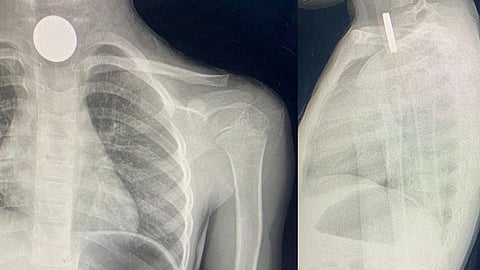

نجح فريق طبي في مستشفى طبرجل العام بمنطقة الجوف، من إنقاذ حياة طفلة ابتلعت قطعتين معدنيتين مما أدى لتوقف التنفس لديها.

وذكرت صحة الجوف – عبر حسابها بموقع تويتر- أن الطفلة تبلغ من العمر 5 سنوات، وانقطع عنها الأوكسجين نتيجة ابتلاعها قطعتين معدنيتين.

وأضافت صحة الجوف، أن الطفلة وصلت لقسم الطوارئ بمستشفى طبرجل العام، وتمكن الفريق الطبي من استخراج القطعتين المعدنيتين، مشيرة إلى أنها خرجت من المستشفى وهي بصحة جيدة حاليا.